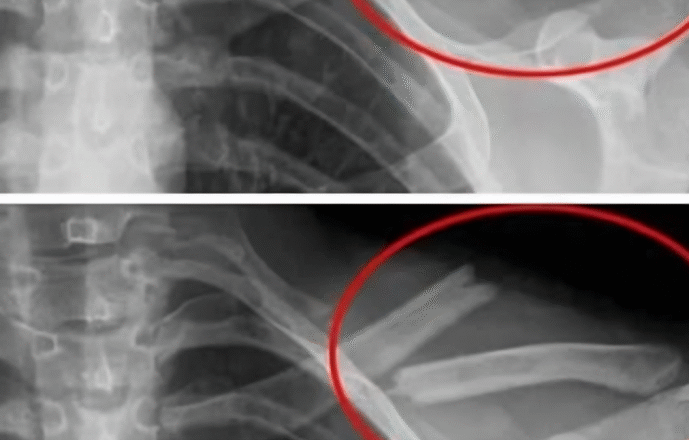

6. Більше міцних кісток

Крім того, дослідження знаходяться ще в початковій стадії, неясно, чому саме, дослідження показали, що навіть одна дієтична газація в день може збільшити перелом бедра на 14%. Існує зв’язок між темами, хто п’є багато газіровок, і більш низькою щільністю кісток, а це може означати, що відмова від газіровок зробить ваші кістки більш здоровими!